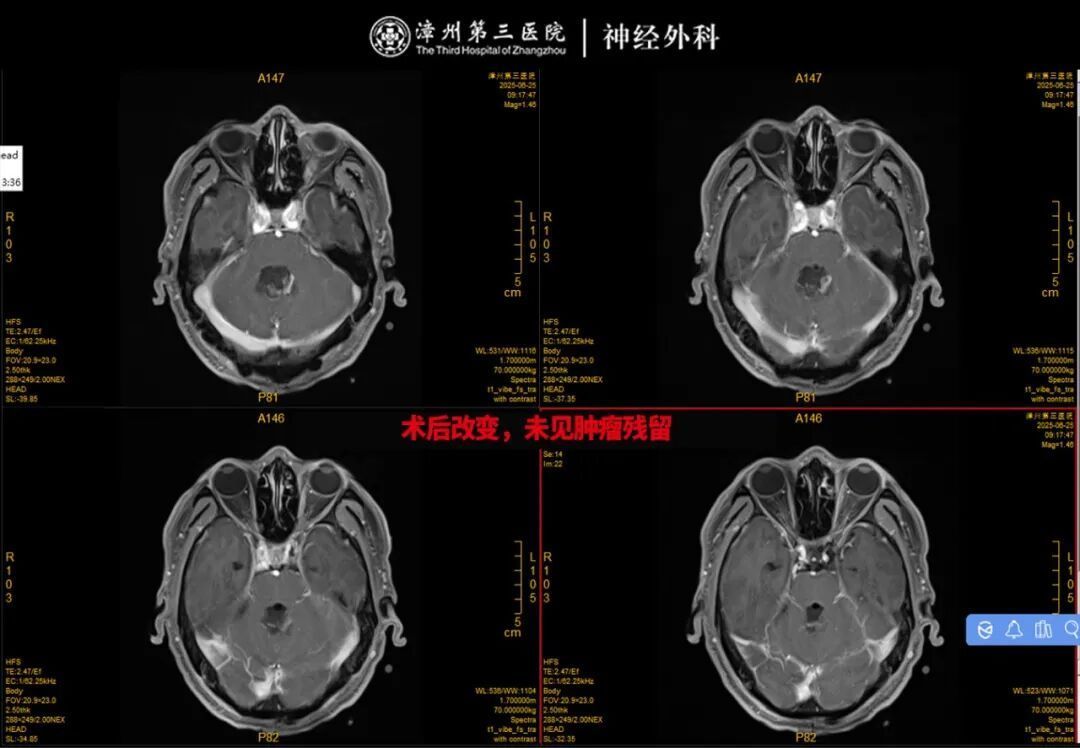

手术本日,在林友城副院长的领导下,手术团队凭借丰富的临床训戒和深通的技巧,环环相扣地操作。他们防御翼翼地分辨病变与周围神经血管的粘连,精确遁藏脑干及伏击功能区,徐徐将占位病变完满切除。扫数手术经由弥留而有序,最终成功完成,术中出血量少,未对周围正常组织变成毁伤。

术后,切除的病变组织被送去作念病理查验。让东谈主喜跃的是,病理收尾显露,这个让群众着急不安的“占位”并非恶性肿瘤,而是表皮样囊肿,一种良性病变。